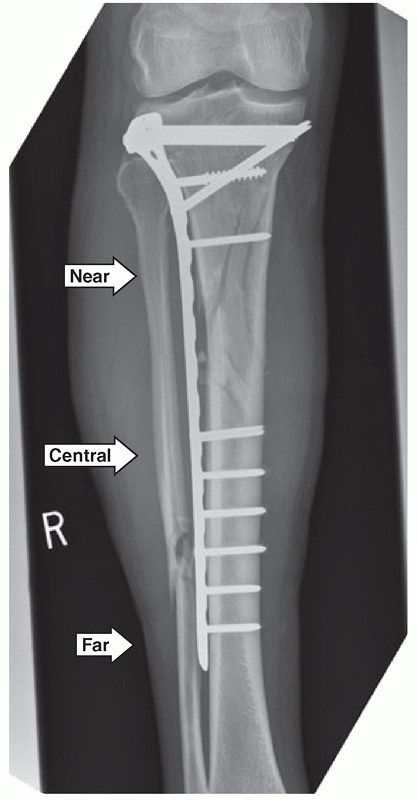

span large areas of comminution as shown in Figure 55-11. Ricci et al.236

have documented a series of 38 patients with proximal tibia fractures,

18 of which were OTA type A fractures. They were treated using a

minimally invasive approach.236 All of the fractures united in satisfactory alignment.

![]() |

|

FIGURE 55-11 A. Anteroposterior and lateral radiographs of a comminuted proximal tibia fracture with an intra-articular extension. B. The fracture was successfully treated with a long locked plate and united uneventfully.